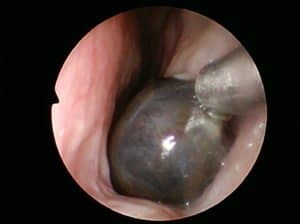

Ear wax impaction with hearing loss

Impacted Ear Wax